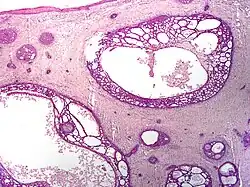

| Type | Histopathology | Other characteristics | Image |

|---|---|---|---|

| Cystic basal-cell carcinoma | Morphologically characterized by dome-shaped, blue-gray cystic nodules.[31]: 647 |

| |